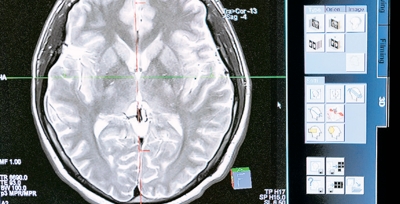

Hallan dos genes que pueden aumentar el riesgo de esquizofrenia

En una nueva investigación publicada en la revista Nature Genetics se identificaron dos genes de riesgo (SRRM2 y AKAP11) causantes de esquizofrenia tras evaluar datos existentes de 35 828 casos y 107 877 controles. Sin embargo, bajo el estudio realizado se encontró que la existencia de un tercer gen (PLO) también estaría vinculado con dicha enfermedad, además de tener conexión con el autismo, lo cual para los investigadores implicaría la creación de nuevas terapias.